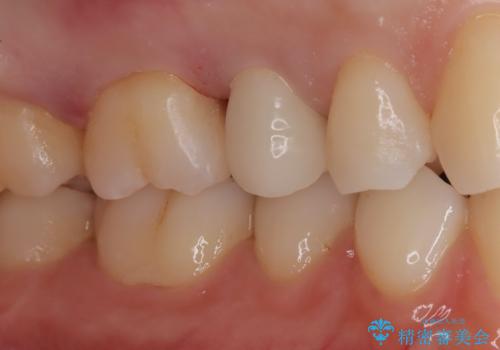

【セラミックインレー】定期検診にて虫歯を発見

- 定期検診にて虫歯を発見したため、セラミッククラウン、セラミックインレーにて治療を行いました。

小臼歯の虫歯は歯髄に近かったため、部分的断髄法にて歯髄を部分的に保存した治療をおこなっています。